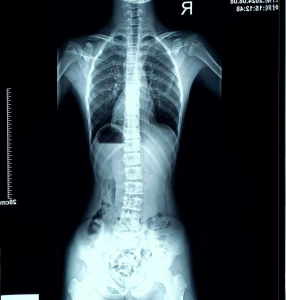

康复前后对比

经过两个多月每周两次的系统性训练,目前进展成果如下:

(胸段16°到近乎0°;腰椎10°到6°)